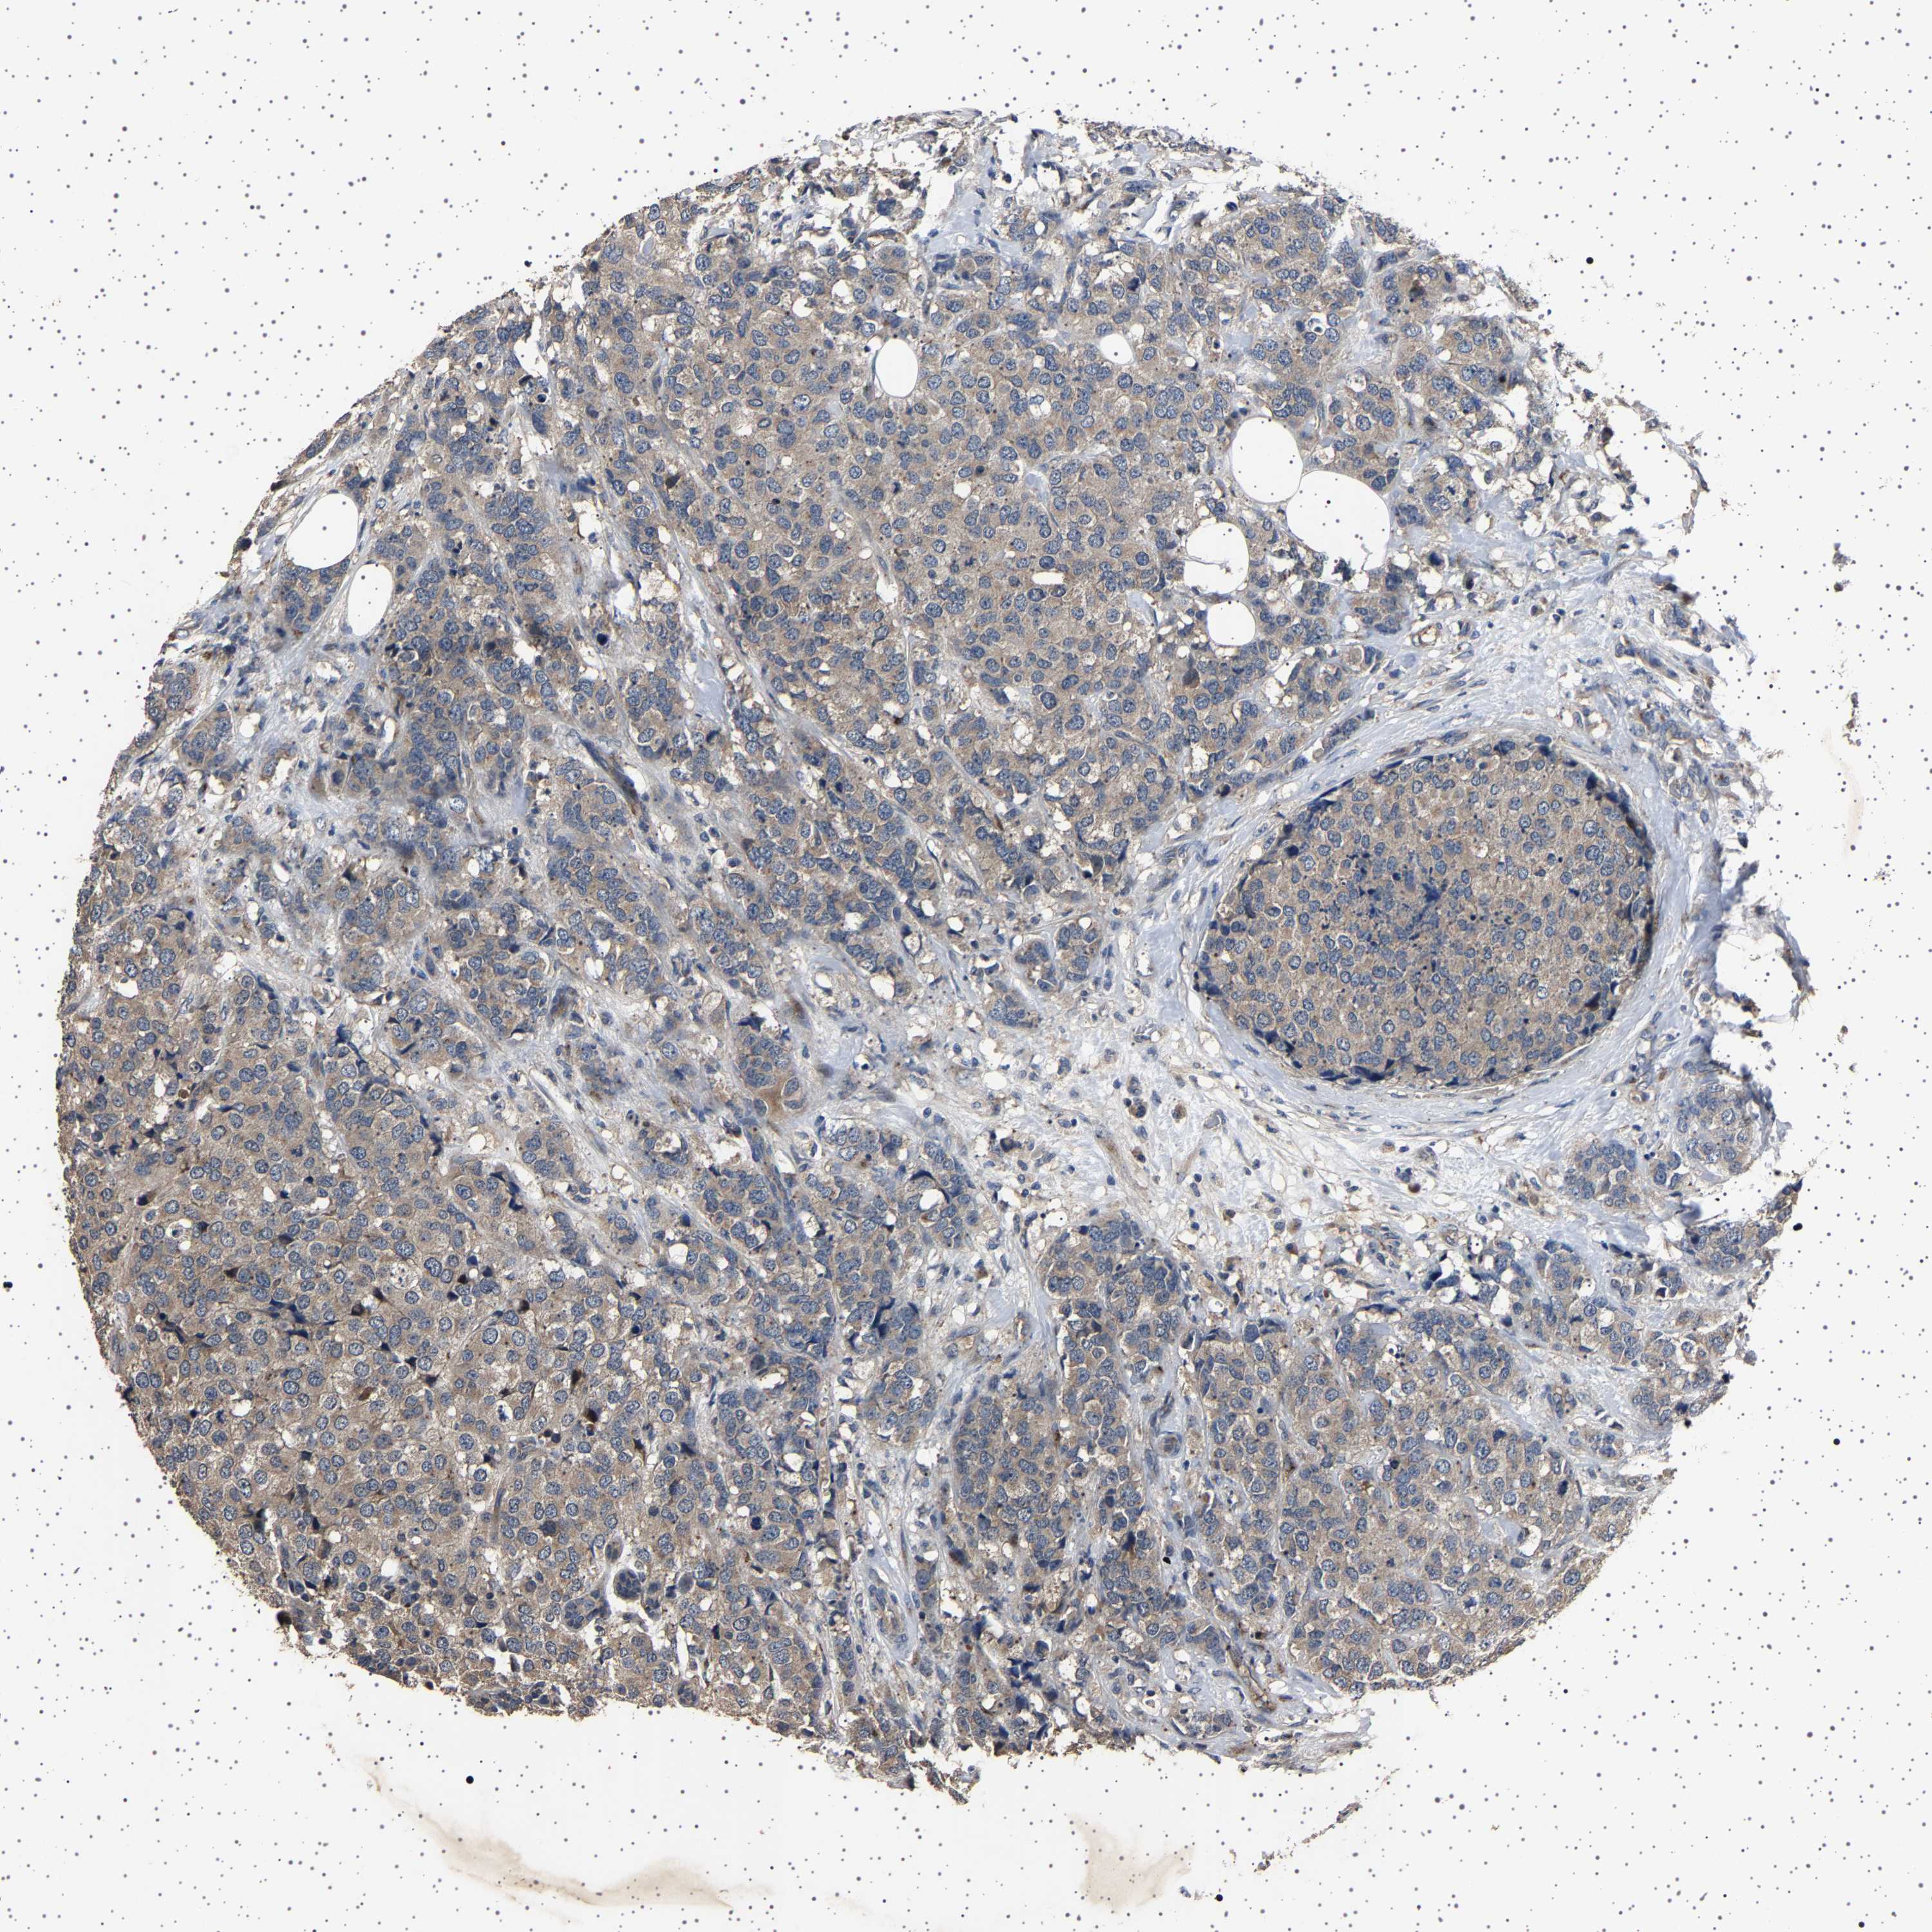

CANCER BREAST CANCER Show tissue menu

BRCA TCGA BRCA VALIDATION PROTEIN EXPRESSION